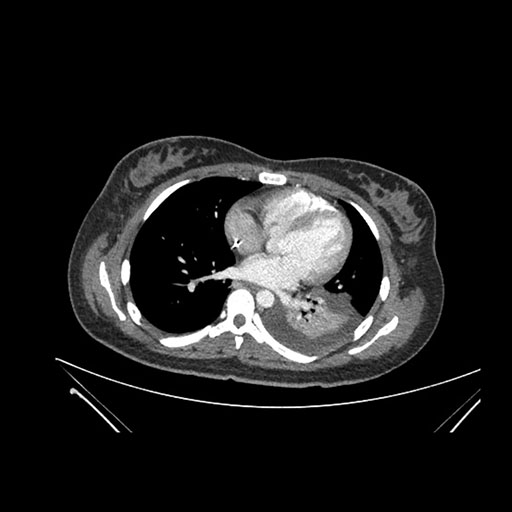

Imaging Analysis

Look through the patient's CT scan to identify any areas of concern for the necessary procedure.

Axial Arterial

Based on initial findings, which issue(s) would you be most concerned about?